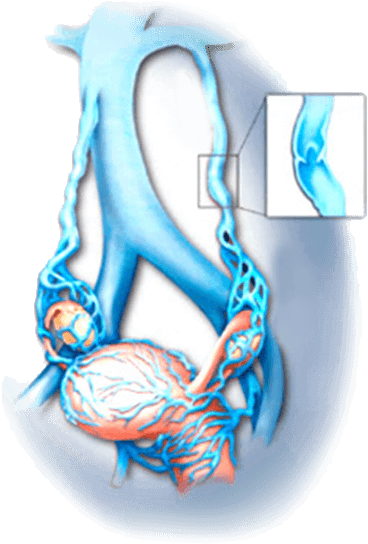

Nagłe zagrożenie

Tworzenie się skrzepów krwi (skrzeplin) wewnątrz naczyń krwionośnych.

Nagłe zerwanie zakrzepu krwi i dostanie się do naczyń mózgu może spowodować udar, paraliż i natychmiastową śmierć.

Nagłe zerwanie zakrzepu krwi i dostanie się do naczyń mózgu może spowodować udar, paraliż i natychmiastową śmierć.

Zakrzepica

żył głębokich

żył głębokich

Nieznośny ból

Ściany żył zostają zaognione, powodując nieznośny ból. Spowolnienie przepływu krwi.

Niebieska skórza nóg. Powstanie owrzodzeń troficznych

zakrzepowe

zapalenie żył

zapalenie żył

Żylaki narządów wewnętrznych

żylaki miednicy

Wpływa na żyły jajników, żyły biodrowe, żylny splot

pęcherza i żyły macicy. Żylaki miednicy mogą prowadzić do chronicznych hemoroidów.

Żylaki przydatków macicy

Żylaki wpływają na macicę. Objawy: ciągnące bóle w

podbrzuszu, wydłużenie czasu trwania miesiączki, dyskomfort podczas stosunku. Zakłócenia w dopływie krwi do jajników są niebezpieczne z powodu rozwoju niepłodności u kobiet.

żylaki przełyku

Wcześniej czy później cienkie ściany żył mogą pęknąć w żołądku lub przełyku,

powodując wewnętrzne krwawienie osoby z krwiopluciem i czarny, żywiczny stolec.

Jest to bezpośrednie zagrożenie dla życia.